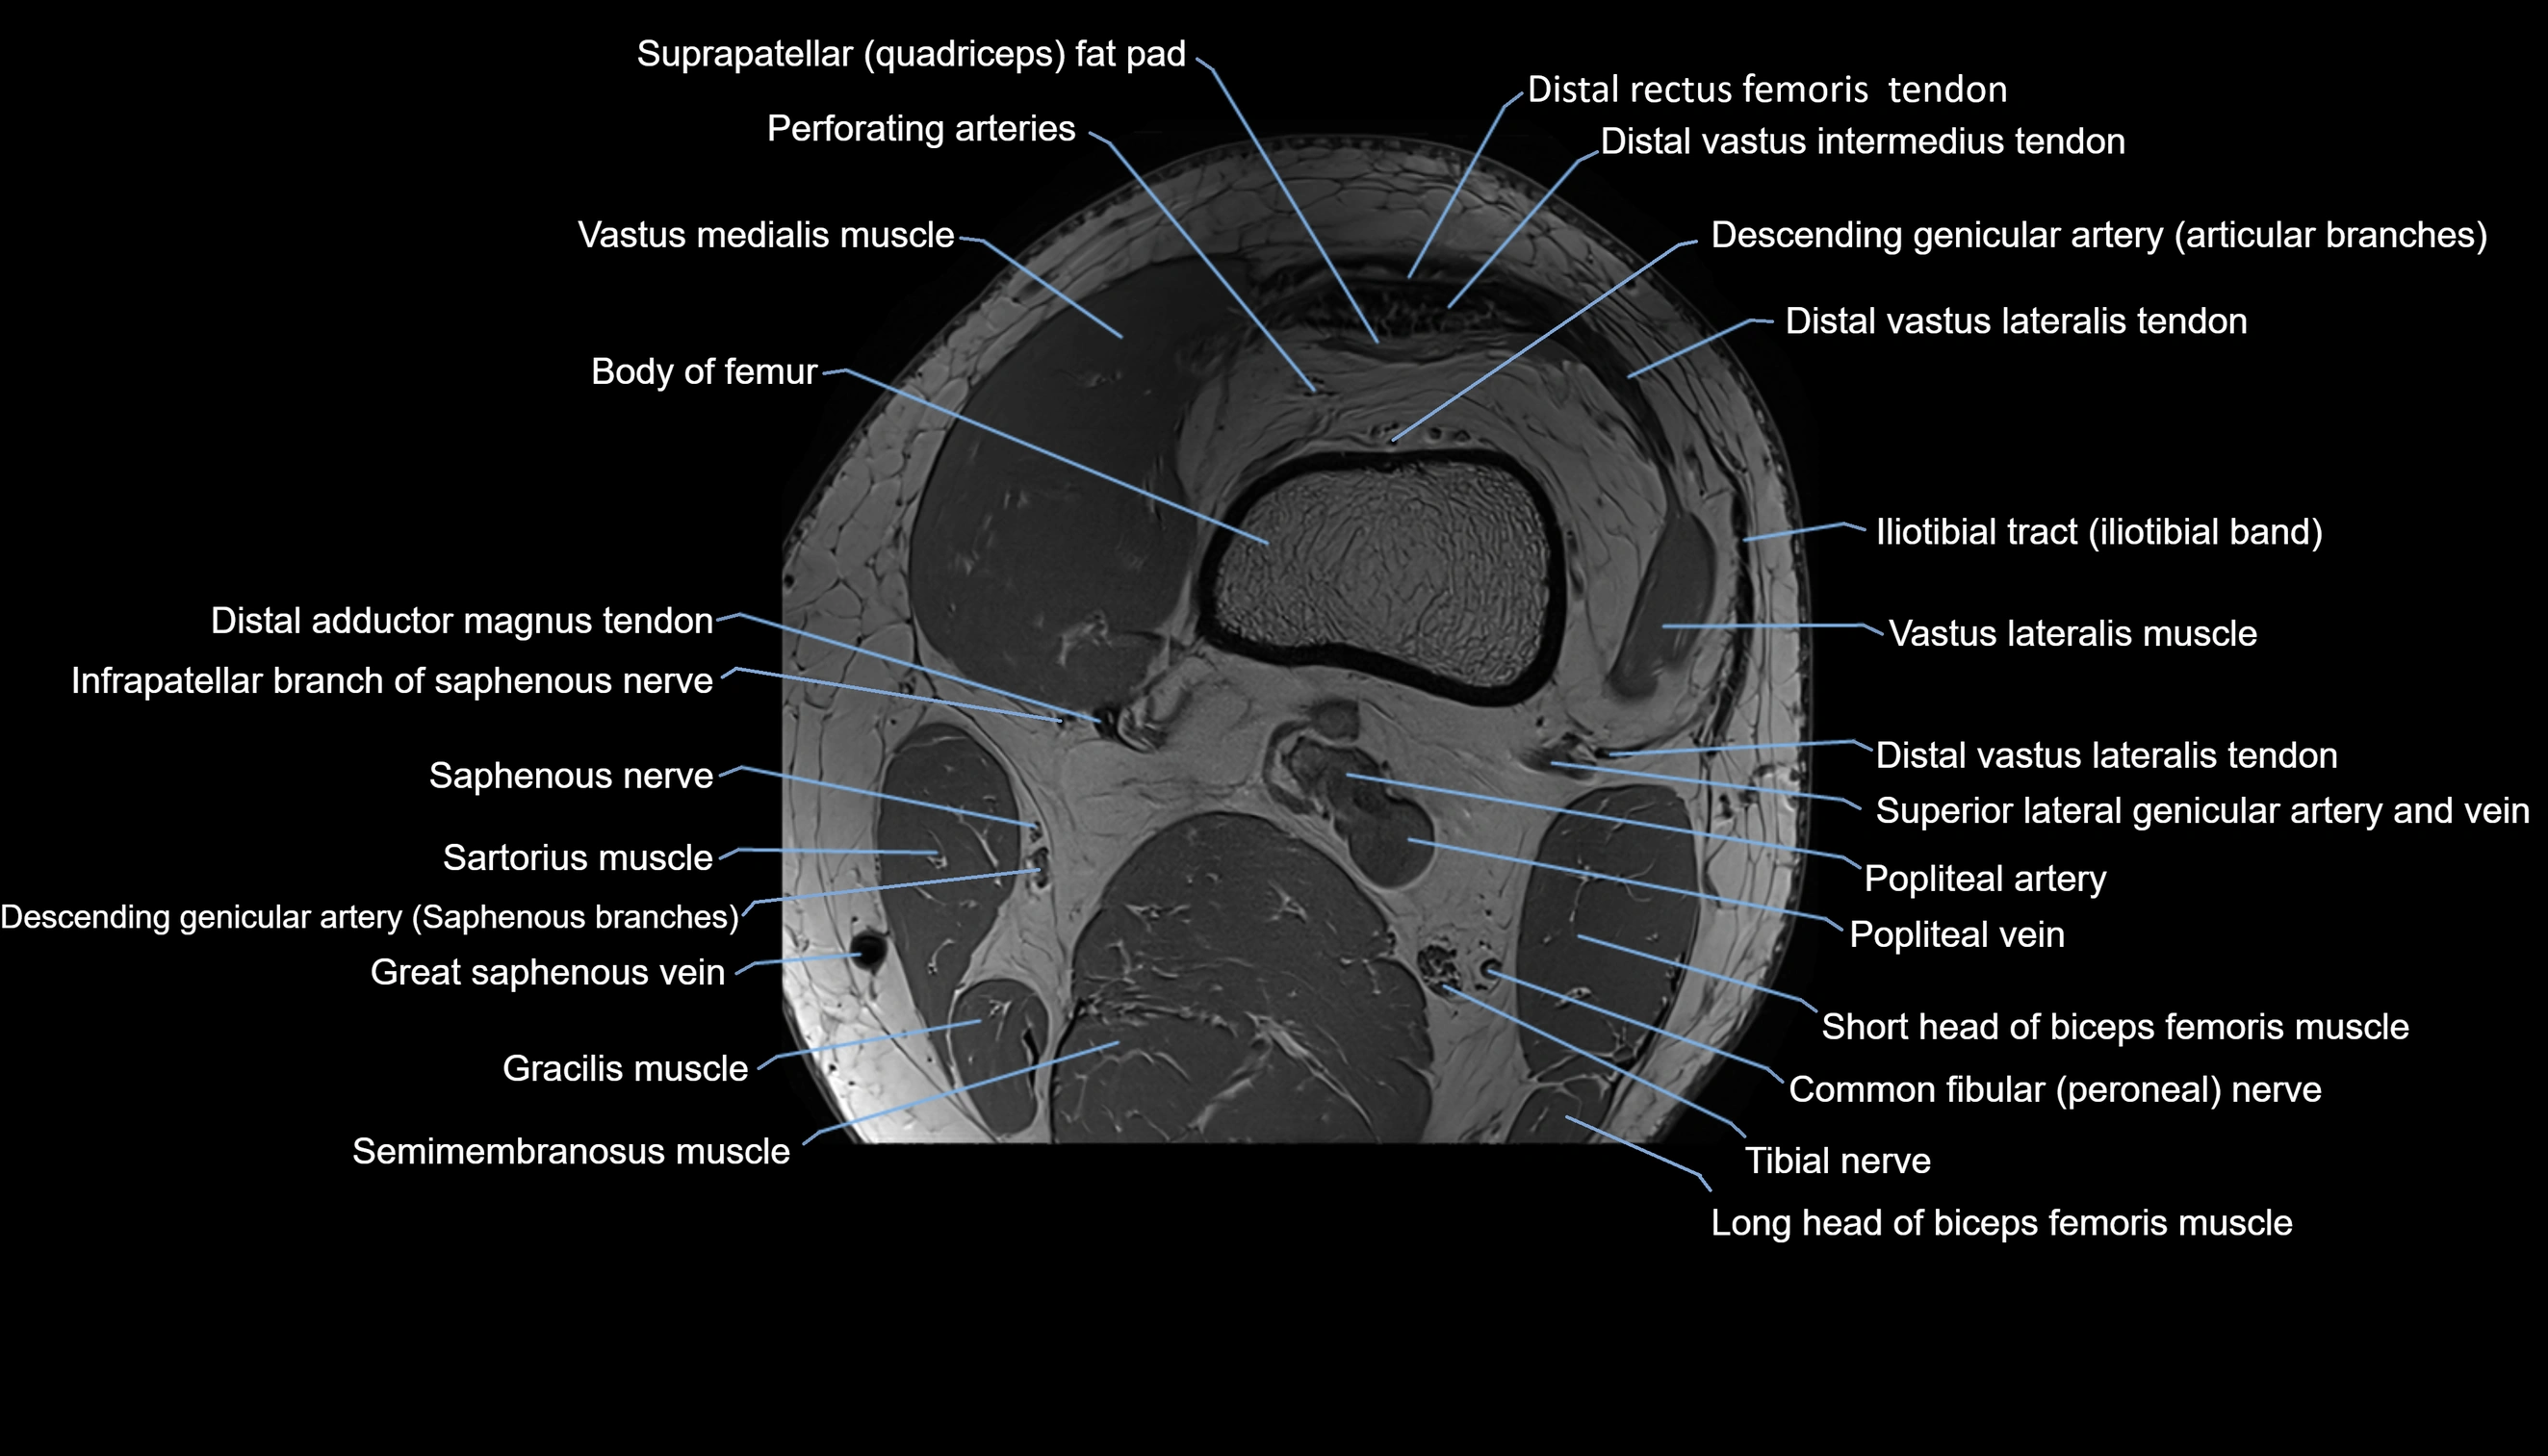

- Body of femur

- Common fibular nerve

- Descending genicular artery (Articular branches)

- Descending genicular artery (Saphenous branch)

- Distal adductor magnus tendon

- Distal rectus femoris tendon

- Distal vastus intermedius tendon

- Distal vastus lateralis tendon

- Infrapatellar branch of saphenous nerve

- Popliteal artery

- Popliteal vein

- Saphenous nerve

- Sartorius muscle

- Semimembranosus muscle

- Superior lateral genicular artery

- Superior lateral genicular vein

- Suprapatellar fat pad

- Tibial nerve

- Vastus lateralis muscle

- Vastus medialis muscle

- great saphenous vein